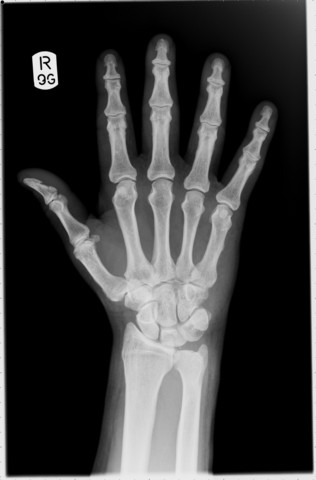

Broke My Wrist

The first week of summer, I had basketball camp at STM. It was called Moore Hoops. As we were doing a drill, a boy beside me cut right in front of me and tripped me! I ended up slamming my right wrist against the hard wood floor, causing a break in the bone. I had to wear a full arm cast for the whole summer!